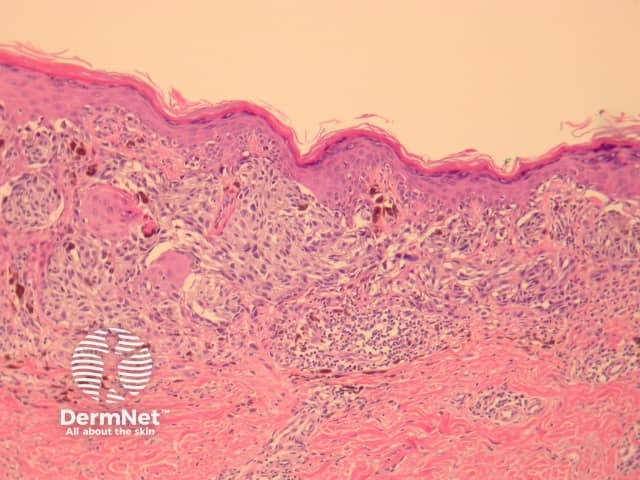

The histological features of lichen planus are:

Pathology of lichen planus